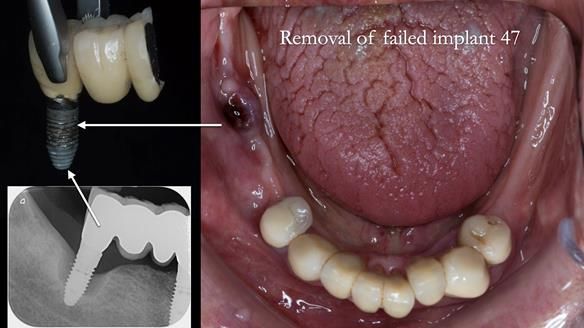

We began with the lower jaw.

A posterior implant 47 had lost integration and was infected. This was removed.

Ken did not want further implant surgery.